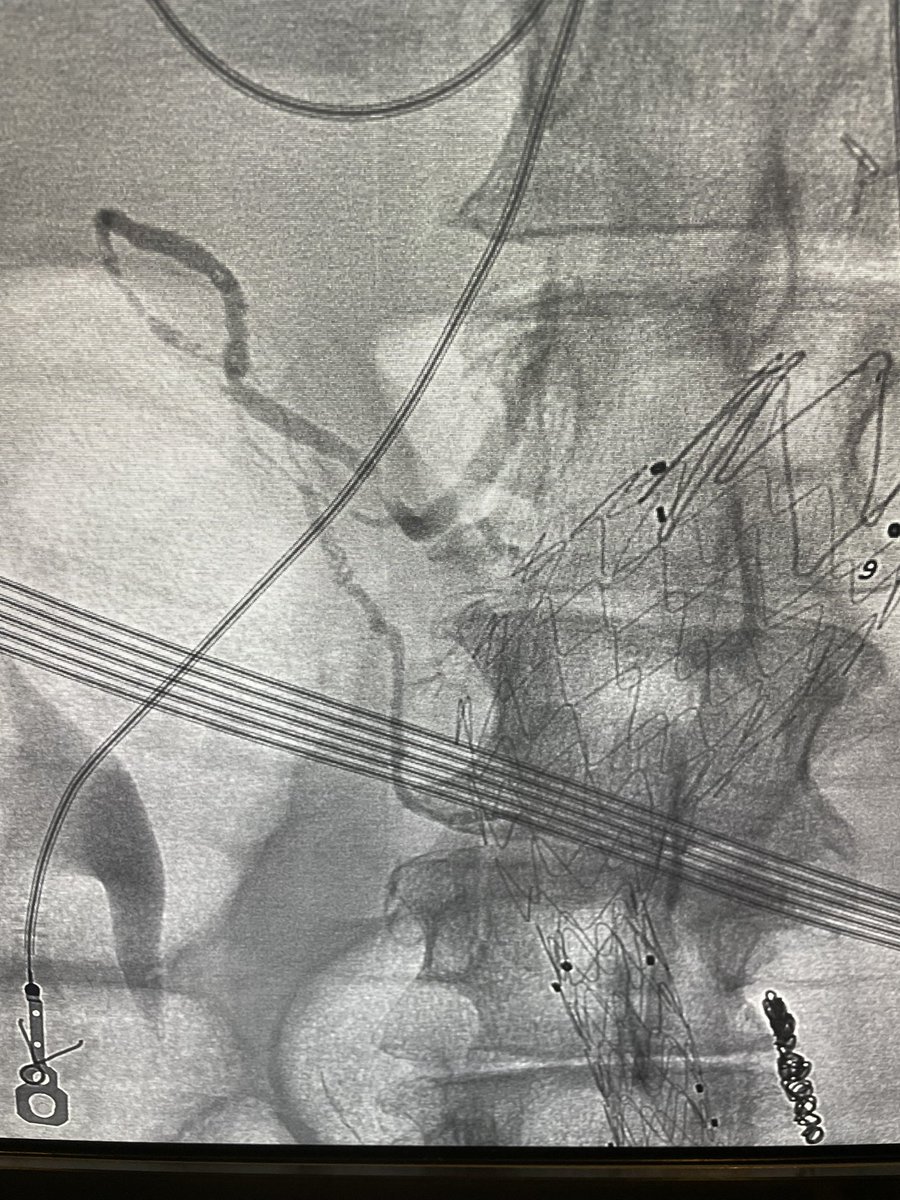

SIR published a new position statement offering recommendations on the management of chronic iliofemoral venous obstruction with endovascular placement of metallic stents. Access the statement on jvir.org to review suggestions and analysis. fal.cn/3Apcy